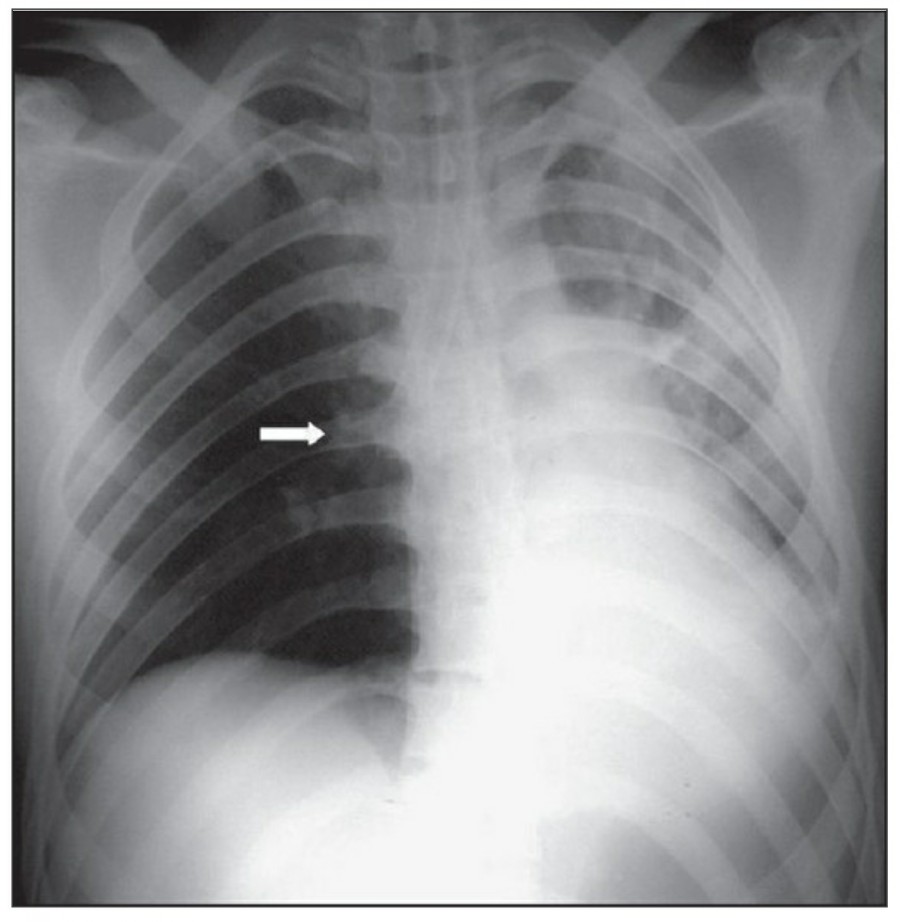

이렇게 얻어진 image는 gravitational and geometrical effect로 인해 mediastinum과 heart가 확대되어서 보이는데, 더욱이 supine position은 pulmonary vasculature의 physiology를 변화시켜서 혈류가 lung apex로 흐르게 한다-이렇게 얻어진 형태는 PA CXR에서는 비정상으로 간주되지만 AP CXR에서는 정상이다. Supine position은 pleural effuson과 air space shadowing의 감별, pneumothorax 발견을 힘들게 한다.

중환자는 협조가 되지 않거나 수술 후 통증 때문에 full inspiration이 쉽지 않으므로 X ray image를 얻기가 어렵다., 따라서 basialr atelectasis와 pulmonary edema의 진단이 어렵고, heart와 mediastinum의 크기가 정확히 나타나지 않게 된다.

CABG를 받은 환자에서 lower lobe atelectasis는 흔한데, 주로 왼쪽에 잘 나타나며 수일 내에 별다른 합병증 없이 회복된다. mediastinum도 약간 확대되어 보일 수 있는데, 만약 그 diameter가 많이 증가한다면 mediastinal hemorrhage 등을 시사할 수 있다. CABG 시행 후 약간의 좌측 pleural effusion은 있을 수 있지만 그 양이 많거나 증가한다면 respiratory compromise를 줄이기 위해 intervention이 필요할 수 있다. 따라서 이전의 사진과 비교를 해서 pleural effusion 양의 변화가 있는지 확인이 필요하겠다.